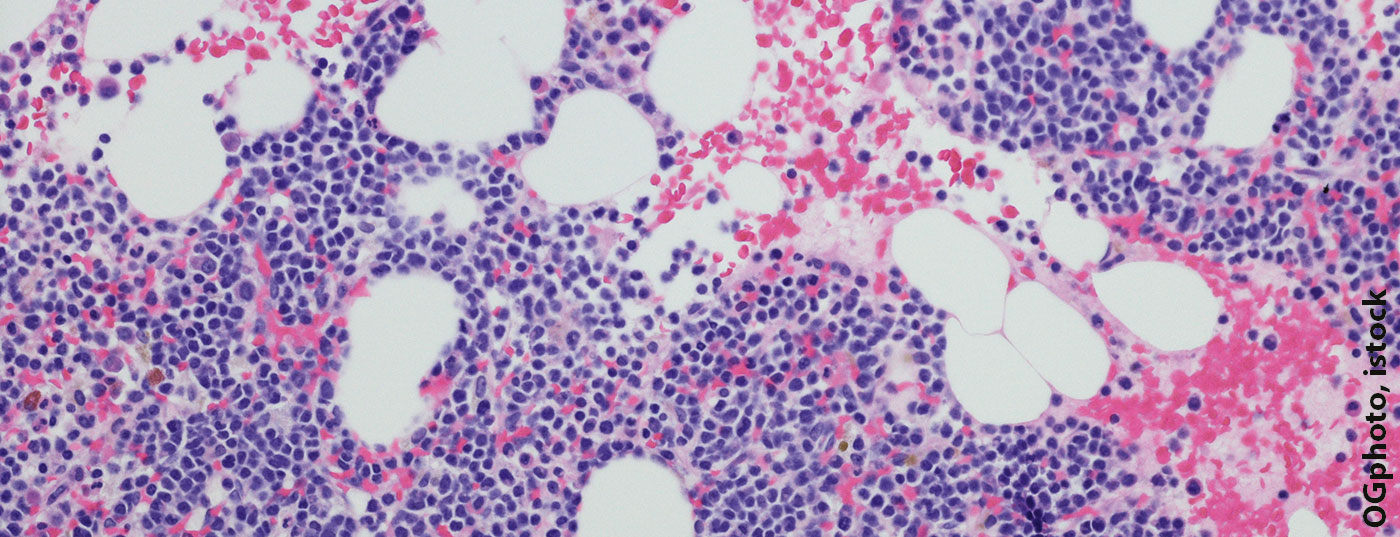

Leukämie, Malignom und Co. auf dem Prüfstand

Das Jahrestreffen der Amerikanischen Gesellschaft für Hämatologie (ASH) gilt weltweit als der wichtigste Kongress zu hämatologischen Erkrankungen. Internationale Experten tauschten sich auch im Dezember 2022 wieder über aktuelle Forschungsergebnisse und die wichtigsten Neuerungen in Diagnostik und Therapie aus. Dabei wurde eine grosse Bandbreite hämatologischer Themen abgedeckt – von der Klassifikation über künstliche Intelligenz bis

hin zu prognostischen Makern.